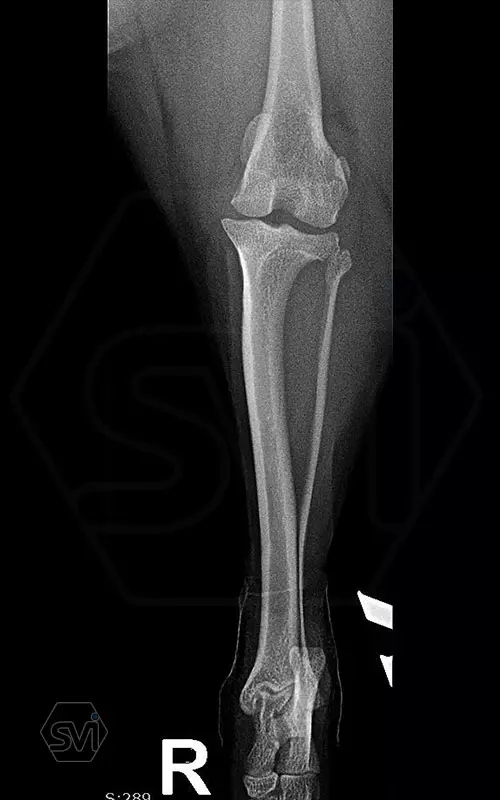

In small dogs, medial patella luxation (MPL) and the rupture of anterior cruciate ligament (RACL) often occur simultaneously. During the surgical procedure, the joint must be stabilized and the patella fixed in the middle axis at the same time.

Between October 2020 and December 2021, we performed 19 TPLO-M surgeries at the Animal Hospital in Nyíregyháza,: 16 times used the mini (2.0 R12) and 3 times the small (2,4 R15) TPLO-M plate.

The experience is very encouraging, we find the system and plates suitable for the simultaneous treatment of MPL and RACL. ( in case of 4/4 pat. lux. also). We will back soon with details.